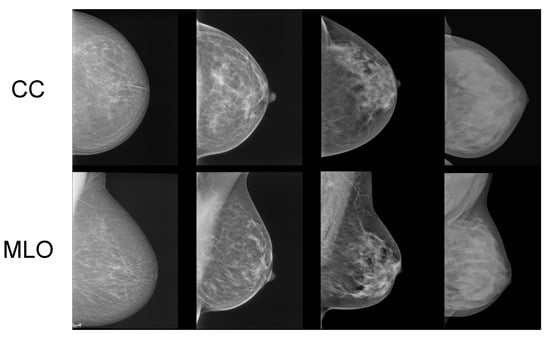

In Figure 1, samples of mammograms with varying densities are provided. Denser tissue appears light within a mammogram, contrasting with the dark appearance of fatty tissue [5]. Potentially harmful growths and tumors also appear light within mammograms. While this contrast makes it easier for radiologists to identify tumors in low-density (fatty) breasts, it notably reduces the sensitivity of mammograms in cases of highly dense breasts [6]. This is because dense tissue can mask potential tumors [6].

Figure 1.

Samples of craniocaudal (CC) and mediolateral oblique (MLO) view mammograms with differing densities [7].